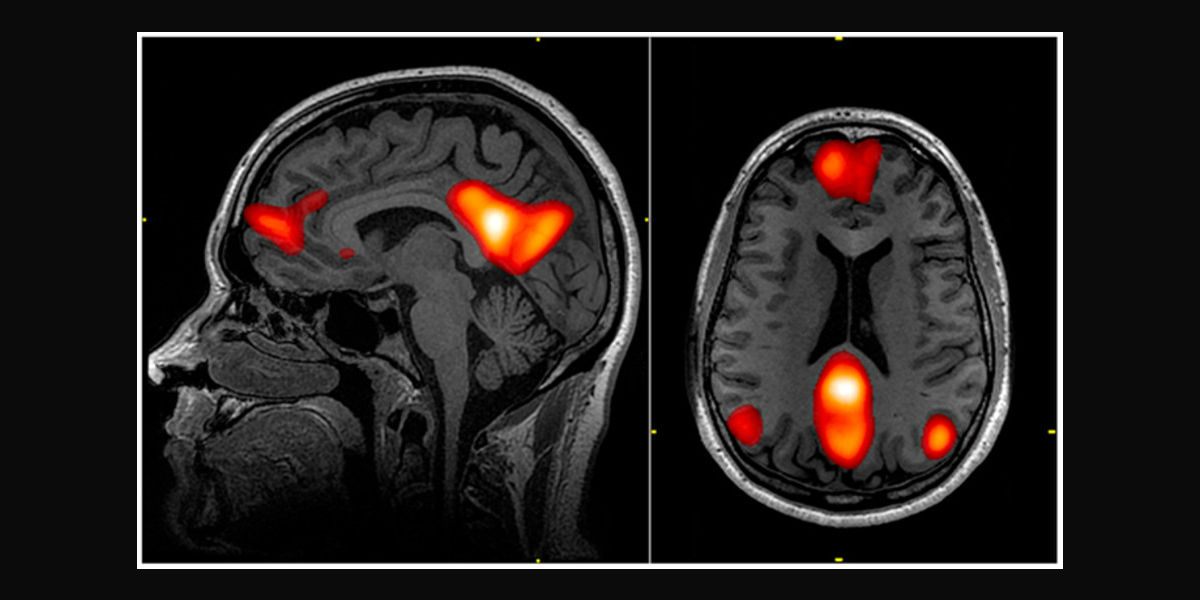

There are various methods of detecting false statements or concealed knowledge, which vary greatly. For example, traditional “lie detection” relies on measuring physiological reactions such as heart rate, blood pressure, pupil dilation and skin sweat response to direct questions, such as “did you kill your wife?” Alternatively, a functional magnetic resonance imaging (fMRI) approach uses brain scans to identify a brain signature for lying.

However, the technology considered by the US researchers, known as “brain fingerprinting”, “guilty knowledge tests” or “concealed information tests”, differs from standard lie detection because it claims to reveal the fingerprint of knowledge stored in the brain. For example, in the case of the hypothetical blue diamond, knowledge of what type of diamond was stolen, where it was stolen, and what type of tools were used to effect the theft.

This technique gathers electrical signals within the brain through the scalp by electroencephalography (EEG), signals which indicate brain responses. Known as the P300 signal, those responses to questions or visual stimuli are assessed for signs that the individual recognises certain pieces of information. The process includes some questions that are neutral in content and used as controls, while others probe for knowledge of facts related to the offence.